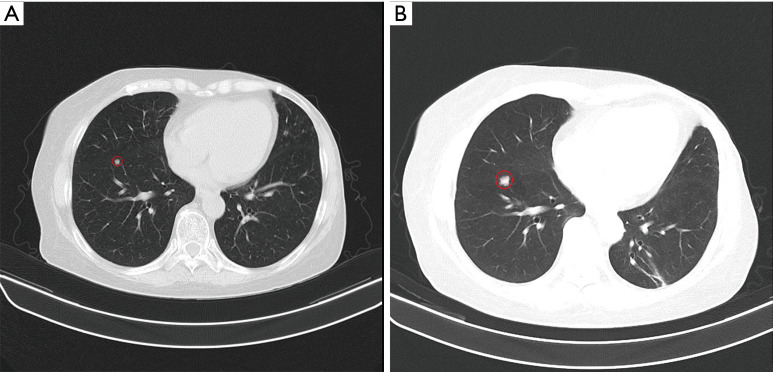

Case description: In this study, we present a case of a 71-year-old woman who was diagnosed with metastatic breast cancer and subsequently developed chronic myeloid leukemia (CML) following her treatment regimen with palbociclib and exemestane. In response to this new diagnosis, the patient commenced therapy with imatinib mesylate while discontinuing palbociclib and receiving exemestane alone for breast cancer. After three months of diligent therapy with imatinib, chronic myeloid leukemia was effectively managed, which permitted the reintroduction of palbociclib at a reduced dosage.